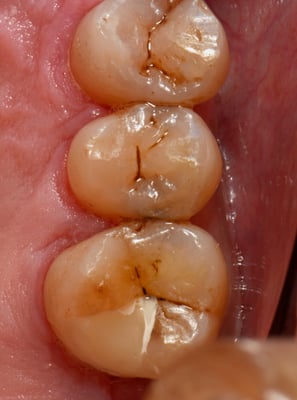

一番左の写真で、どこに虫歯があるかわかるでしょうか?虫歯の進展度を知るためにはレントゲンは欠かせませんが、レントゲンを撮影しなくても、自然光に近い明るい視野の下で、拡大してじっくり観察すれば、早期発見、早期治療に最も役立つのが顕微鏡です。これも当院のベテラン衛生士が最初に気付いた虫歯です。自覚症状がでてからでは、歯髄を保存できる可能性が低くなってしまいます。この症例も、歯髄を除去ぜす(根管治療をしないで)保存できました。

自然光に近い明るい光の下で、拡大して、じっくり観察しなければ、早期に発見出来ない虫歯が多いのです。